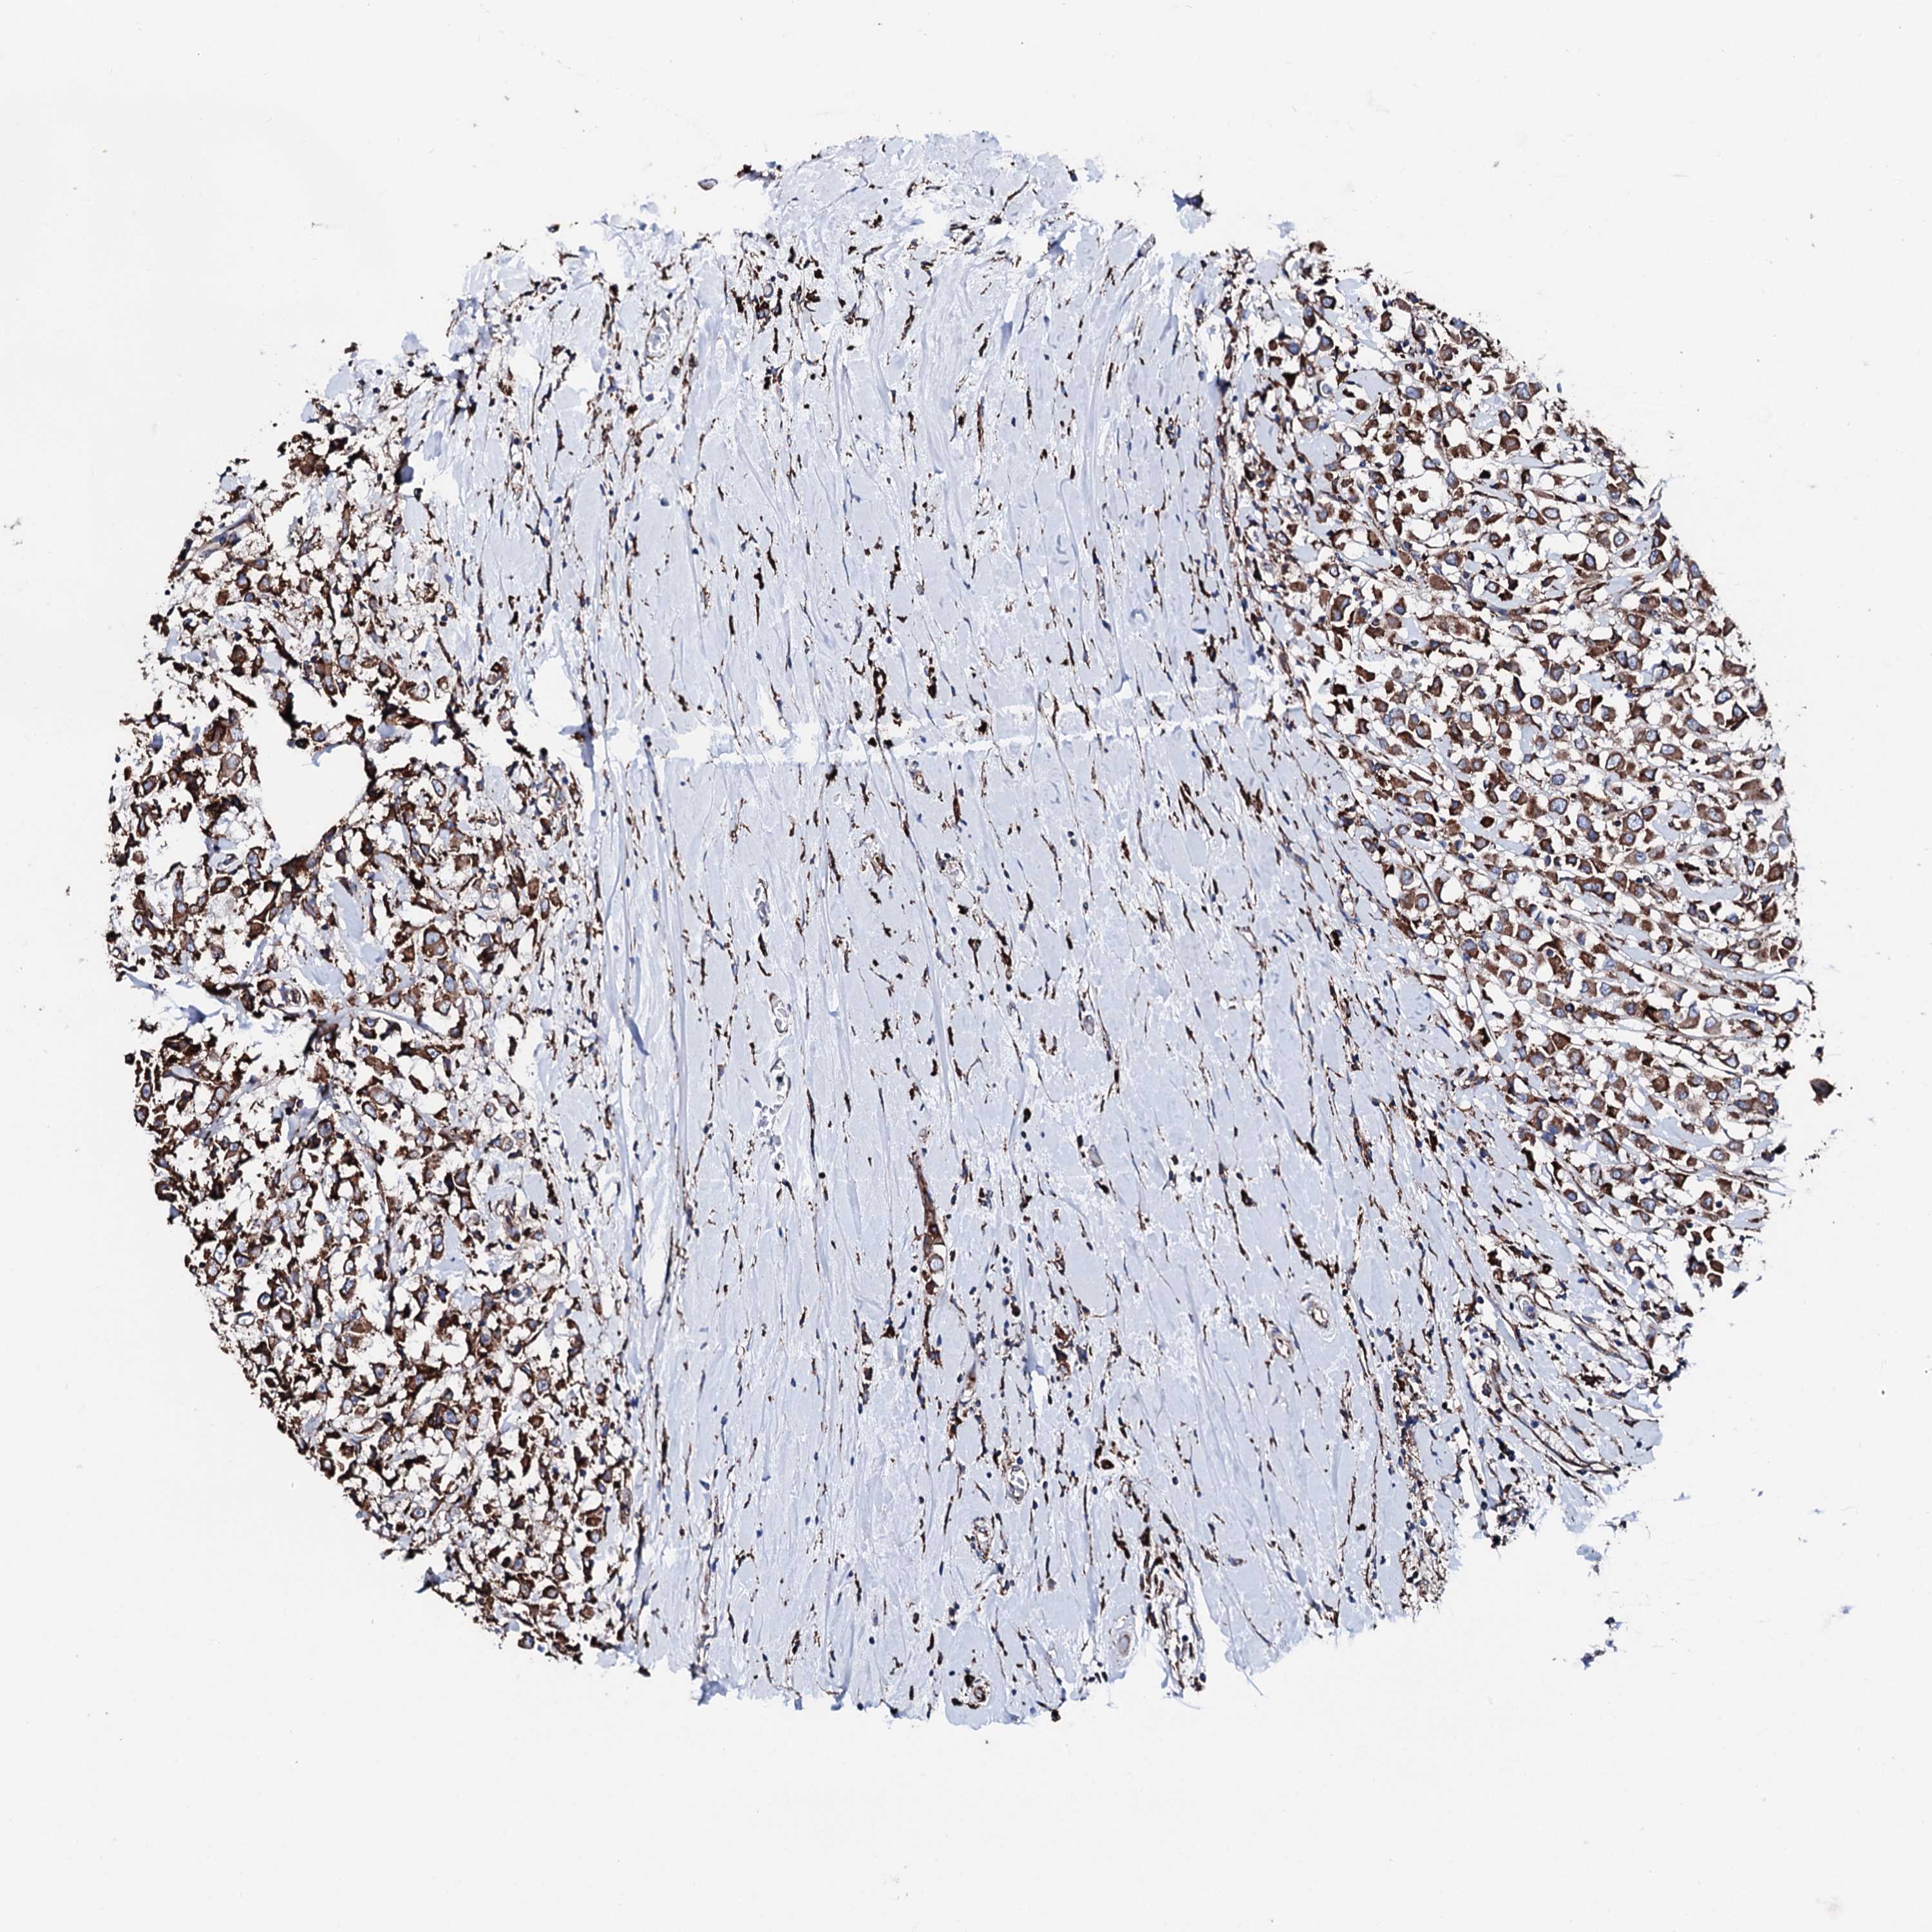

CANCER BREAST CANCER Show tissue menu

BRCA TCGA BRCA VALIDATION PROTEIN EXPRESSION